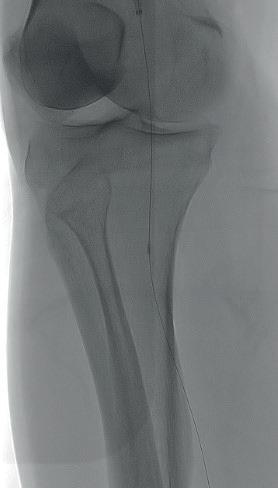

Diagnostic angiogram demonstrated a right popliteal occlusion extending into his proximal tibial vessels (Figure 1). An 0.014” wire was able to easily cross the lesion and pass into the posterior tibial vessel. Intravascular ultrasound (IVUS) demonstrated chronic intraluminal thrombus

with limited evidence of atherosclerosis (Figure 2). A 2.0mm Auryon laser catheter was used to perform a simultaneous athrectomy-thrombectomy (Figure 3). After a single pass, repeat angiogram demonstrated >70% luminal gain (Figure 4). Low pressure (2atm) balloon angioplasty was then performed (Figure 5). Completion angiogram (Figure 6) demonstrated no residual stenosis, with brisk flow into the posterior tibial vessel. The patient developed a palpable posterior tibial pulse, and, at six months, has no claudication symptoms.